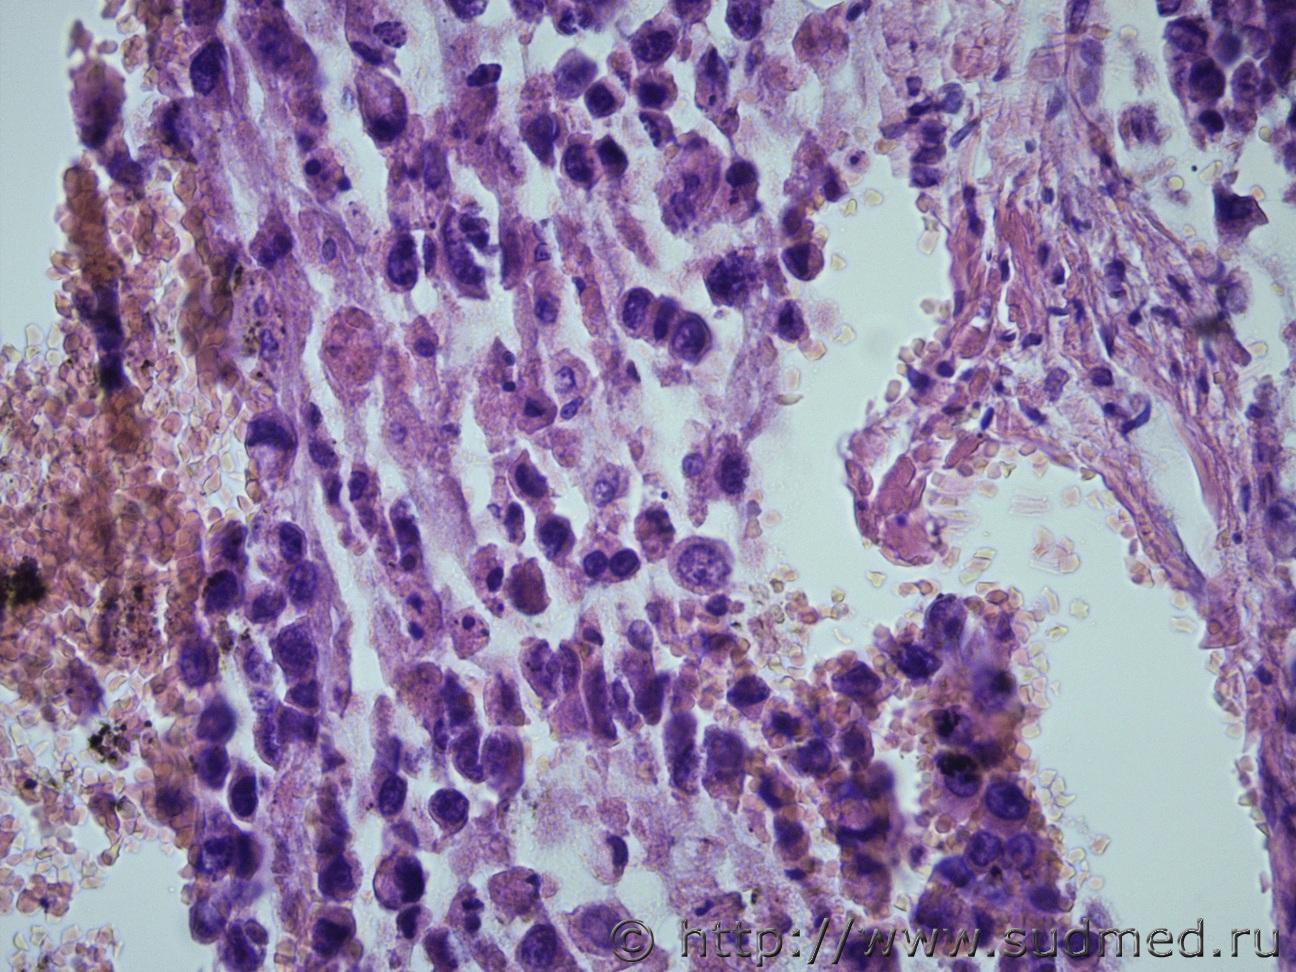

Ув. коллеги. Жен 60 лет. Образование в желудке и в печени. Материал взят не очень удачно, в желудке нечего нет. А в печени опухоль. Перстневидные клетки есть, но не много, местами озера слизи. Могу ли я в данном случая по метастазу поставить рак. Судебная медицина - Прикрепленное изображениеСудебная медицина - Прикрепленное изображениеСудебная медицина - Прикрепленное изображениеСудебная медицина - Прикрепленное изображение

Перстневидноклеточный рак.

Коллоидный( слизистый рак) , либо аденкарцинома с перстневидноклеточным типом.